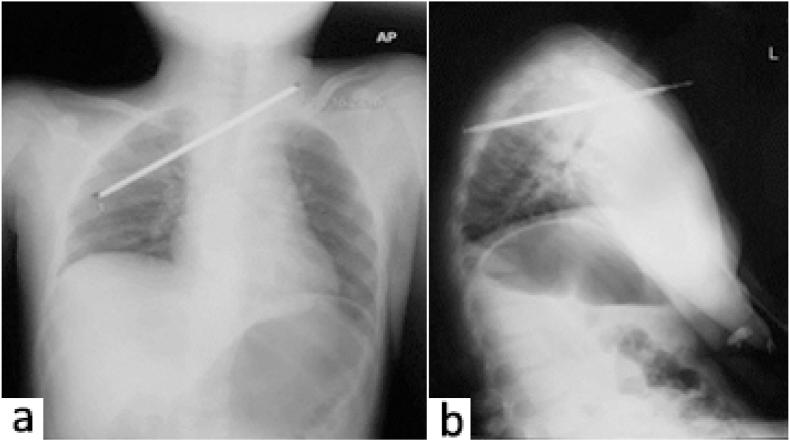

Here, we report a case of a hemodynamically stable 9-year-old boy presenting with a stab wound by a fishing arrow. CT scan showed the fishing arrow projection at the suprasternal notch extended to the right hemithorax where the tip was near the brachiocephalic artery posterior wall. A sternotomy exploration and preservation of the proximal brachiocephalic artery, subclavian artery, and common carotid artery was done. We found a 0.5 cm rupture on the brachiocephalic truncus and performed a direct suture repair.

在此,我们报告一例血流动力学稳定的9岁男孩,因鱼叉刺伤就诊。CT扫描显示鱼叉从胸骨上切迹刺入,延伸至右半胸,尖端靠近头臂干动脉后壁。进行了胸骨切开探查,并保留了近端头臂干动脉、锁骨下动脉和颈总动脉。我们发现头臂干有一处0.5厘米的破裂,并进行了直接缝合修复。